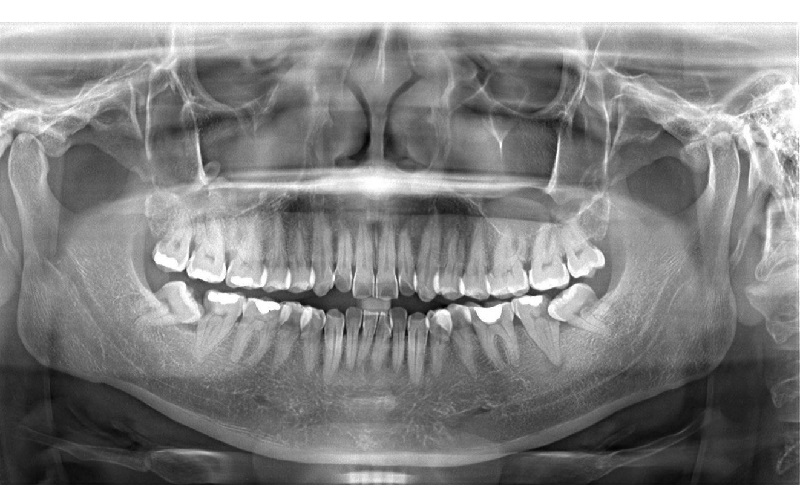

3.3. X quang toàn hàm (Panorama/Panorex)

– Ghi lại hình ảnh toàn bộ hai hàm răng, xương hàm, khớp thái dương hàm trên một phim.

– Dùng để kiểm tra răng khôn, mọc lệch, nang – u xương hàm, theo dõi niềng răng, cấy implant…